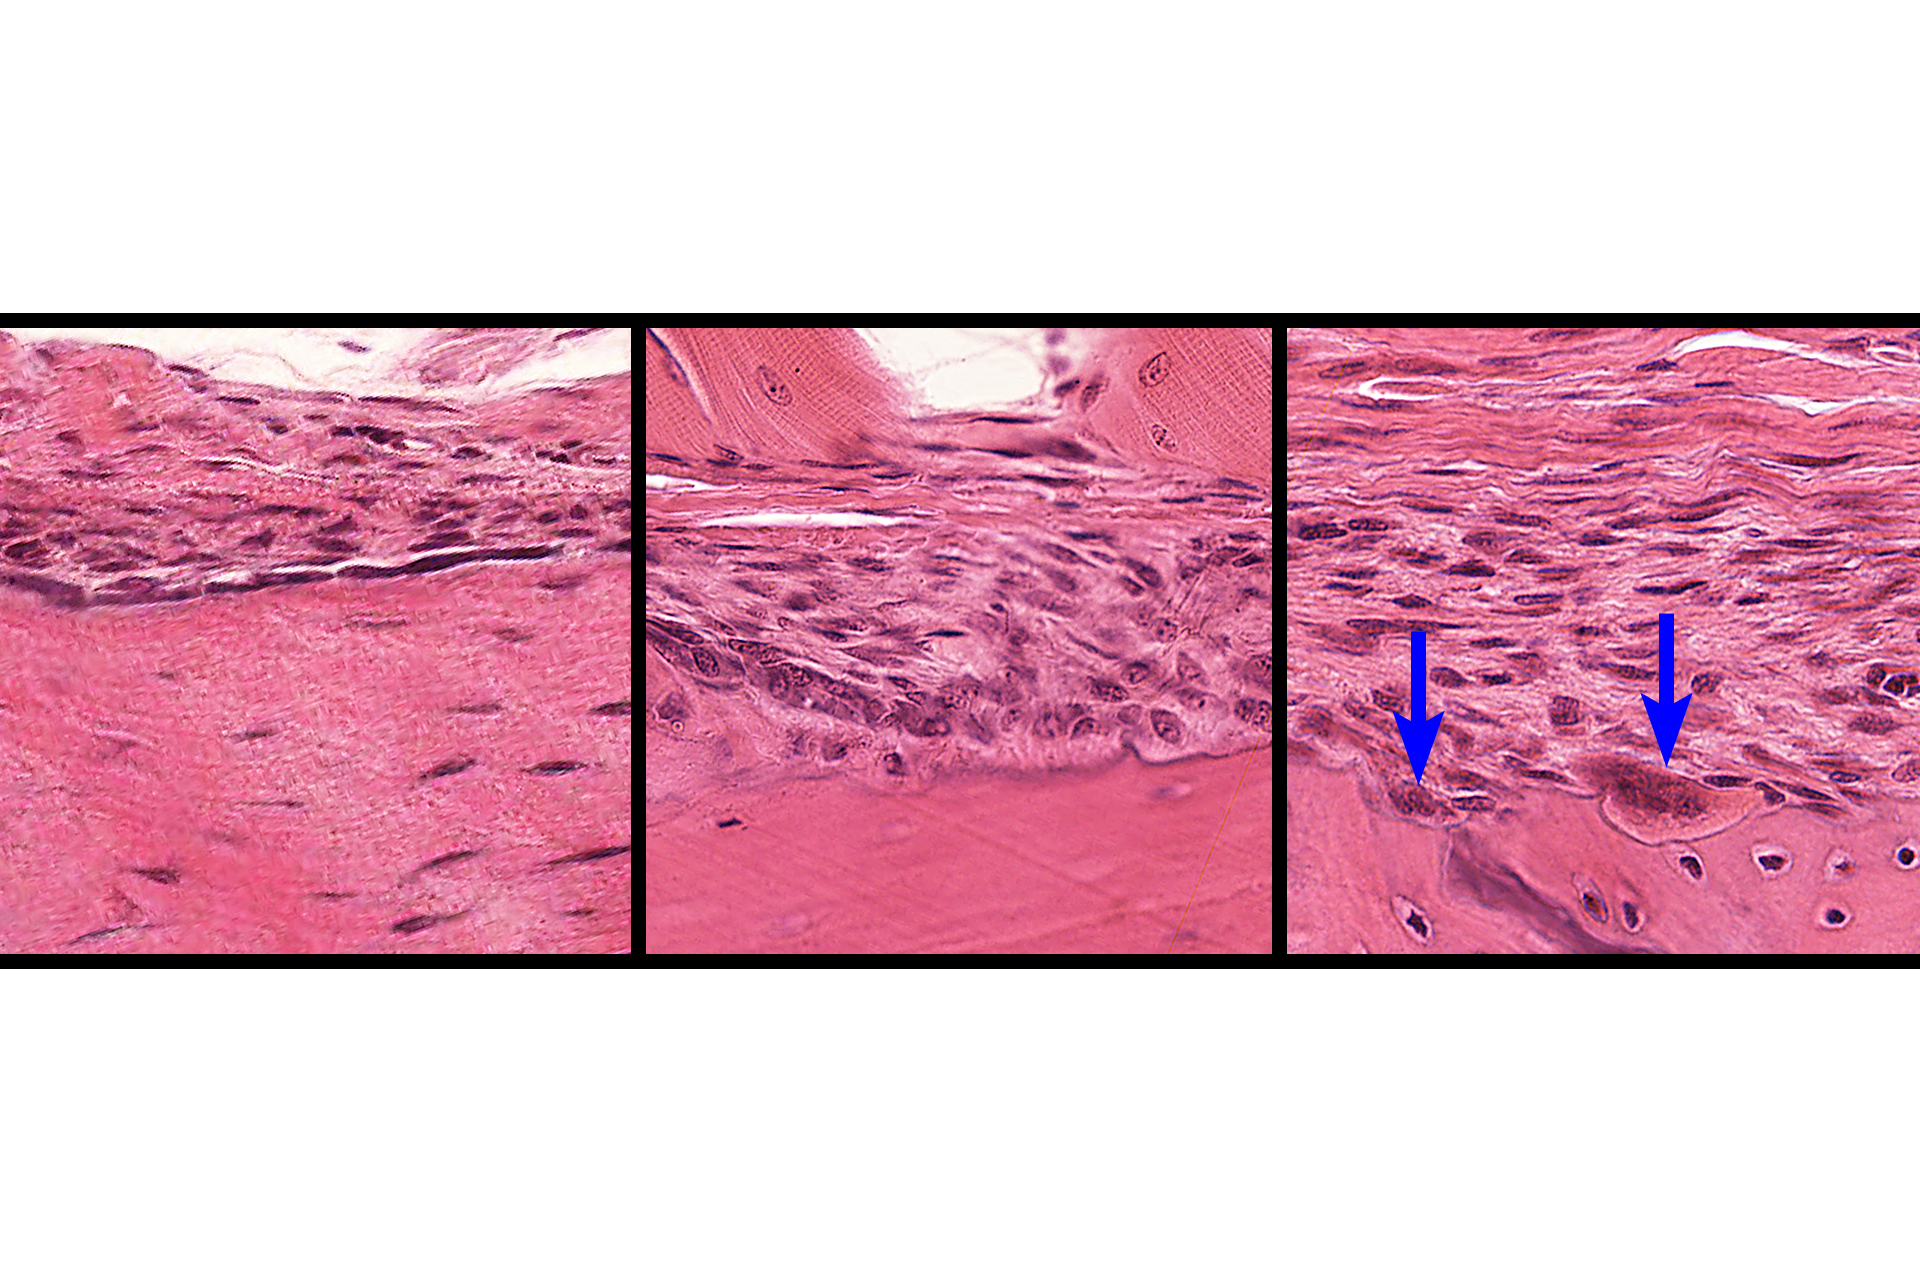

These images show the surface coverings of bone. The outer surface (top image) is covered by a periosteum, the inner surface (bottom image) is lined by endosteum. A low magnification, cross section of the diaphysis is shown in the inset. 10x, 800x, 800x.

Cells of the endosteum and periosteum > <p>In non-active regions of both periosteum and endosteum, bone lining cells are most prevalent (left panel). These cells also include osteoprogenitor cells. In areas of active bone deposition (center panel), cuboidal osteoblasts are present; areas of bone resorption (right panel) are marked by the presence of osteoclasts (arrows).  </p>

In non-active regions of both periosteum and endosteum, bone lining cells are most prevalent (left panel). These cells also include osteoprogenitor cells. In areas of active bone deposition (center panel), cuboidal osteoblasts are present; areas of bone resorption (right panel) are marked by the presence of osteoclasts (arrows).